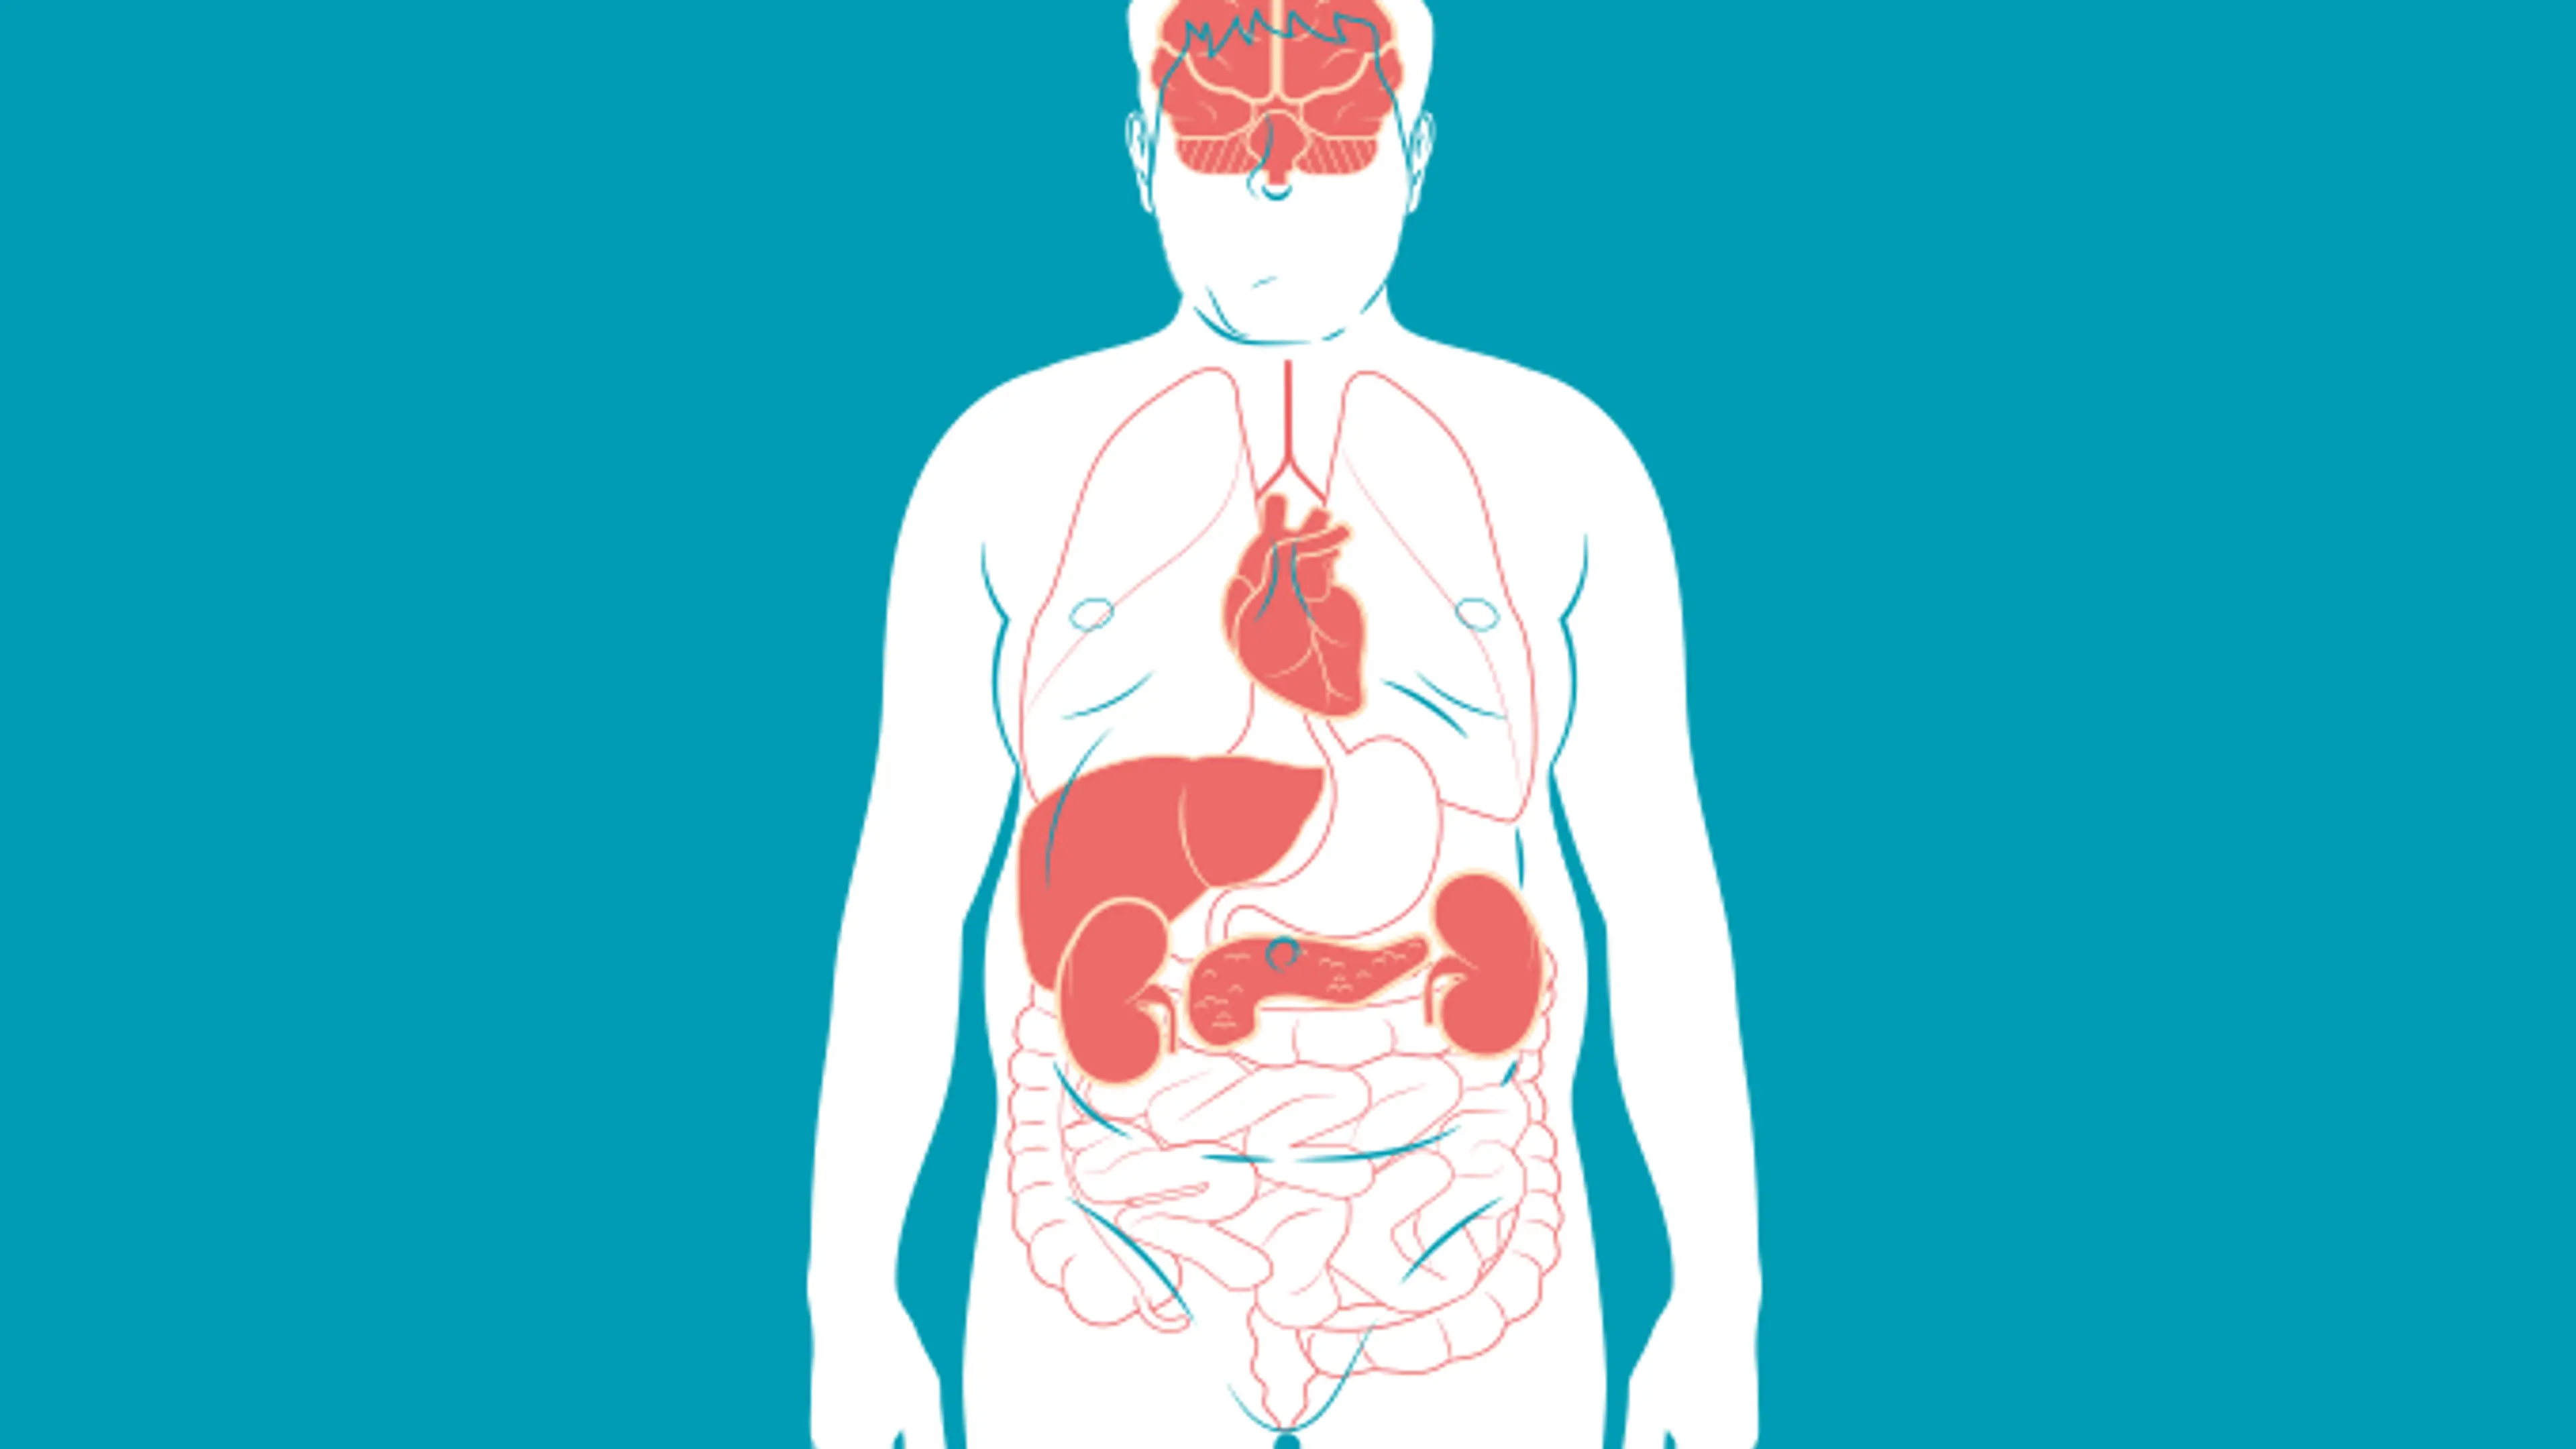

Glicose alta

Glicose > 110 mg/dL

Insulina em jejum > 13 mg/dL

HDL baixo

Homens > 40 mg/dL

Mulheres < 50 mg/dL

Pressão Alta

Sistólica >130 mmHg

Diastólica > 85 mmHg

Triglicerídeos

Acima de 150 mg/dL